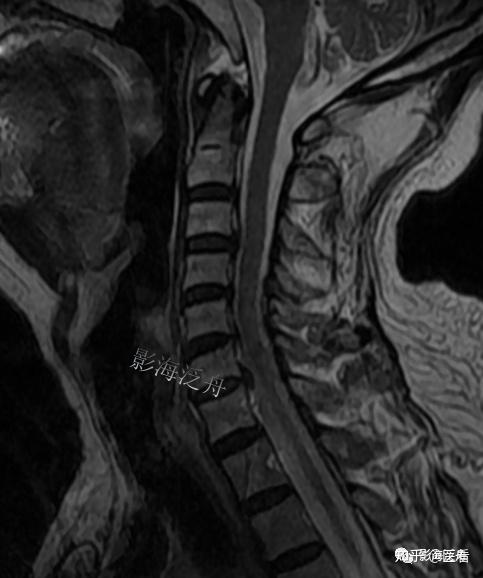

典型病例颈椎后纵韧带钙化mr

颈椎后纵韧带骨化一例

颈椎后纵韧带钙化典型病例 - 好大夫在线